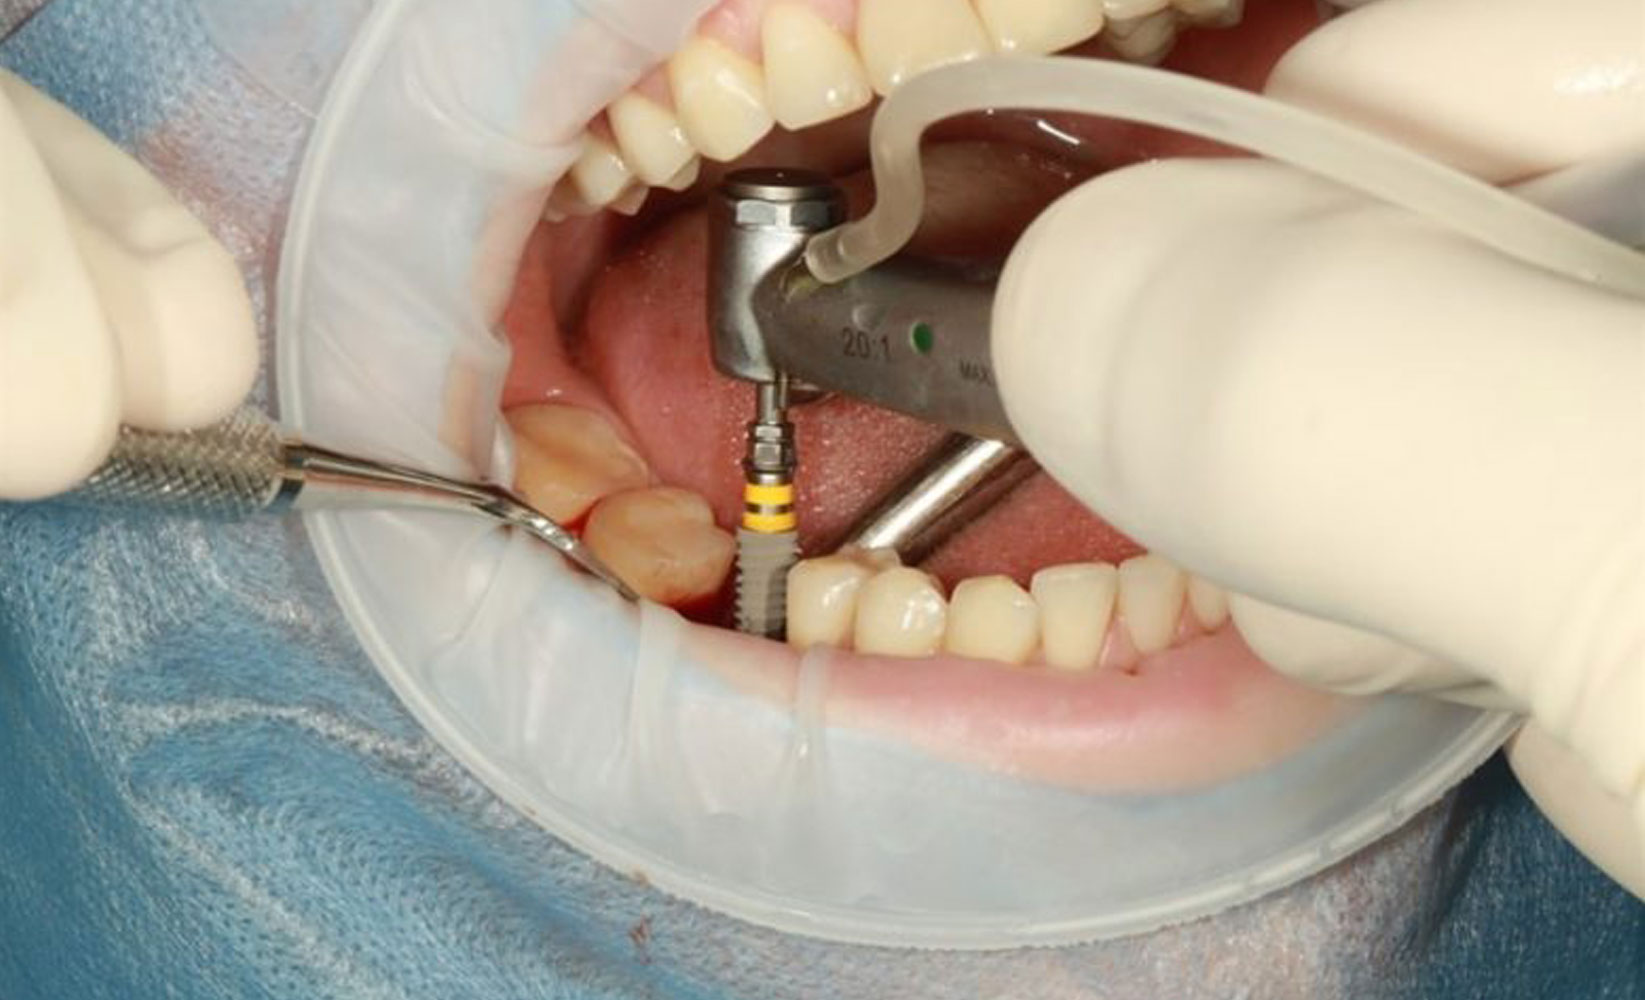

Placing The Implant

• Thanks to modern dentistry techniques, it’s possible to make the implant placement procedure comfortable and pain-free.

• The procedure starts with the jawbone preparation, and the surgeon then makes a cut to expose the bone for drilling holes. The holes are kept deep enough for the Implant to be appropriately placed and deep into the bone, like the root.

• The doctor may require bone grafting in cases where the bone is weak or lacks the strength to support implant surgery. The surgeon then waits for the jawbone to heal and places the metal screw in it.

• The second surgery will be simpler than the first, where a new incision is made to expose the heads of the implants.

Abutment Placement

• You may need another surgery to place the abutment (the piece where the crown will attach), but only after healing. This procedure is relatively simple, typically done with anesthesia in an outpatient setting.

• The dentist will re-open the wound to attach the abutment to the Dental Implant during the procedure. A temporary crown will be given for 4 to 6 weeks to let the gums around the abutment heal. Such a crown is softer, which can cushion the Implant and may stress the soft tissues that can help in healing.